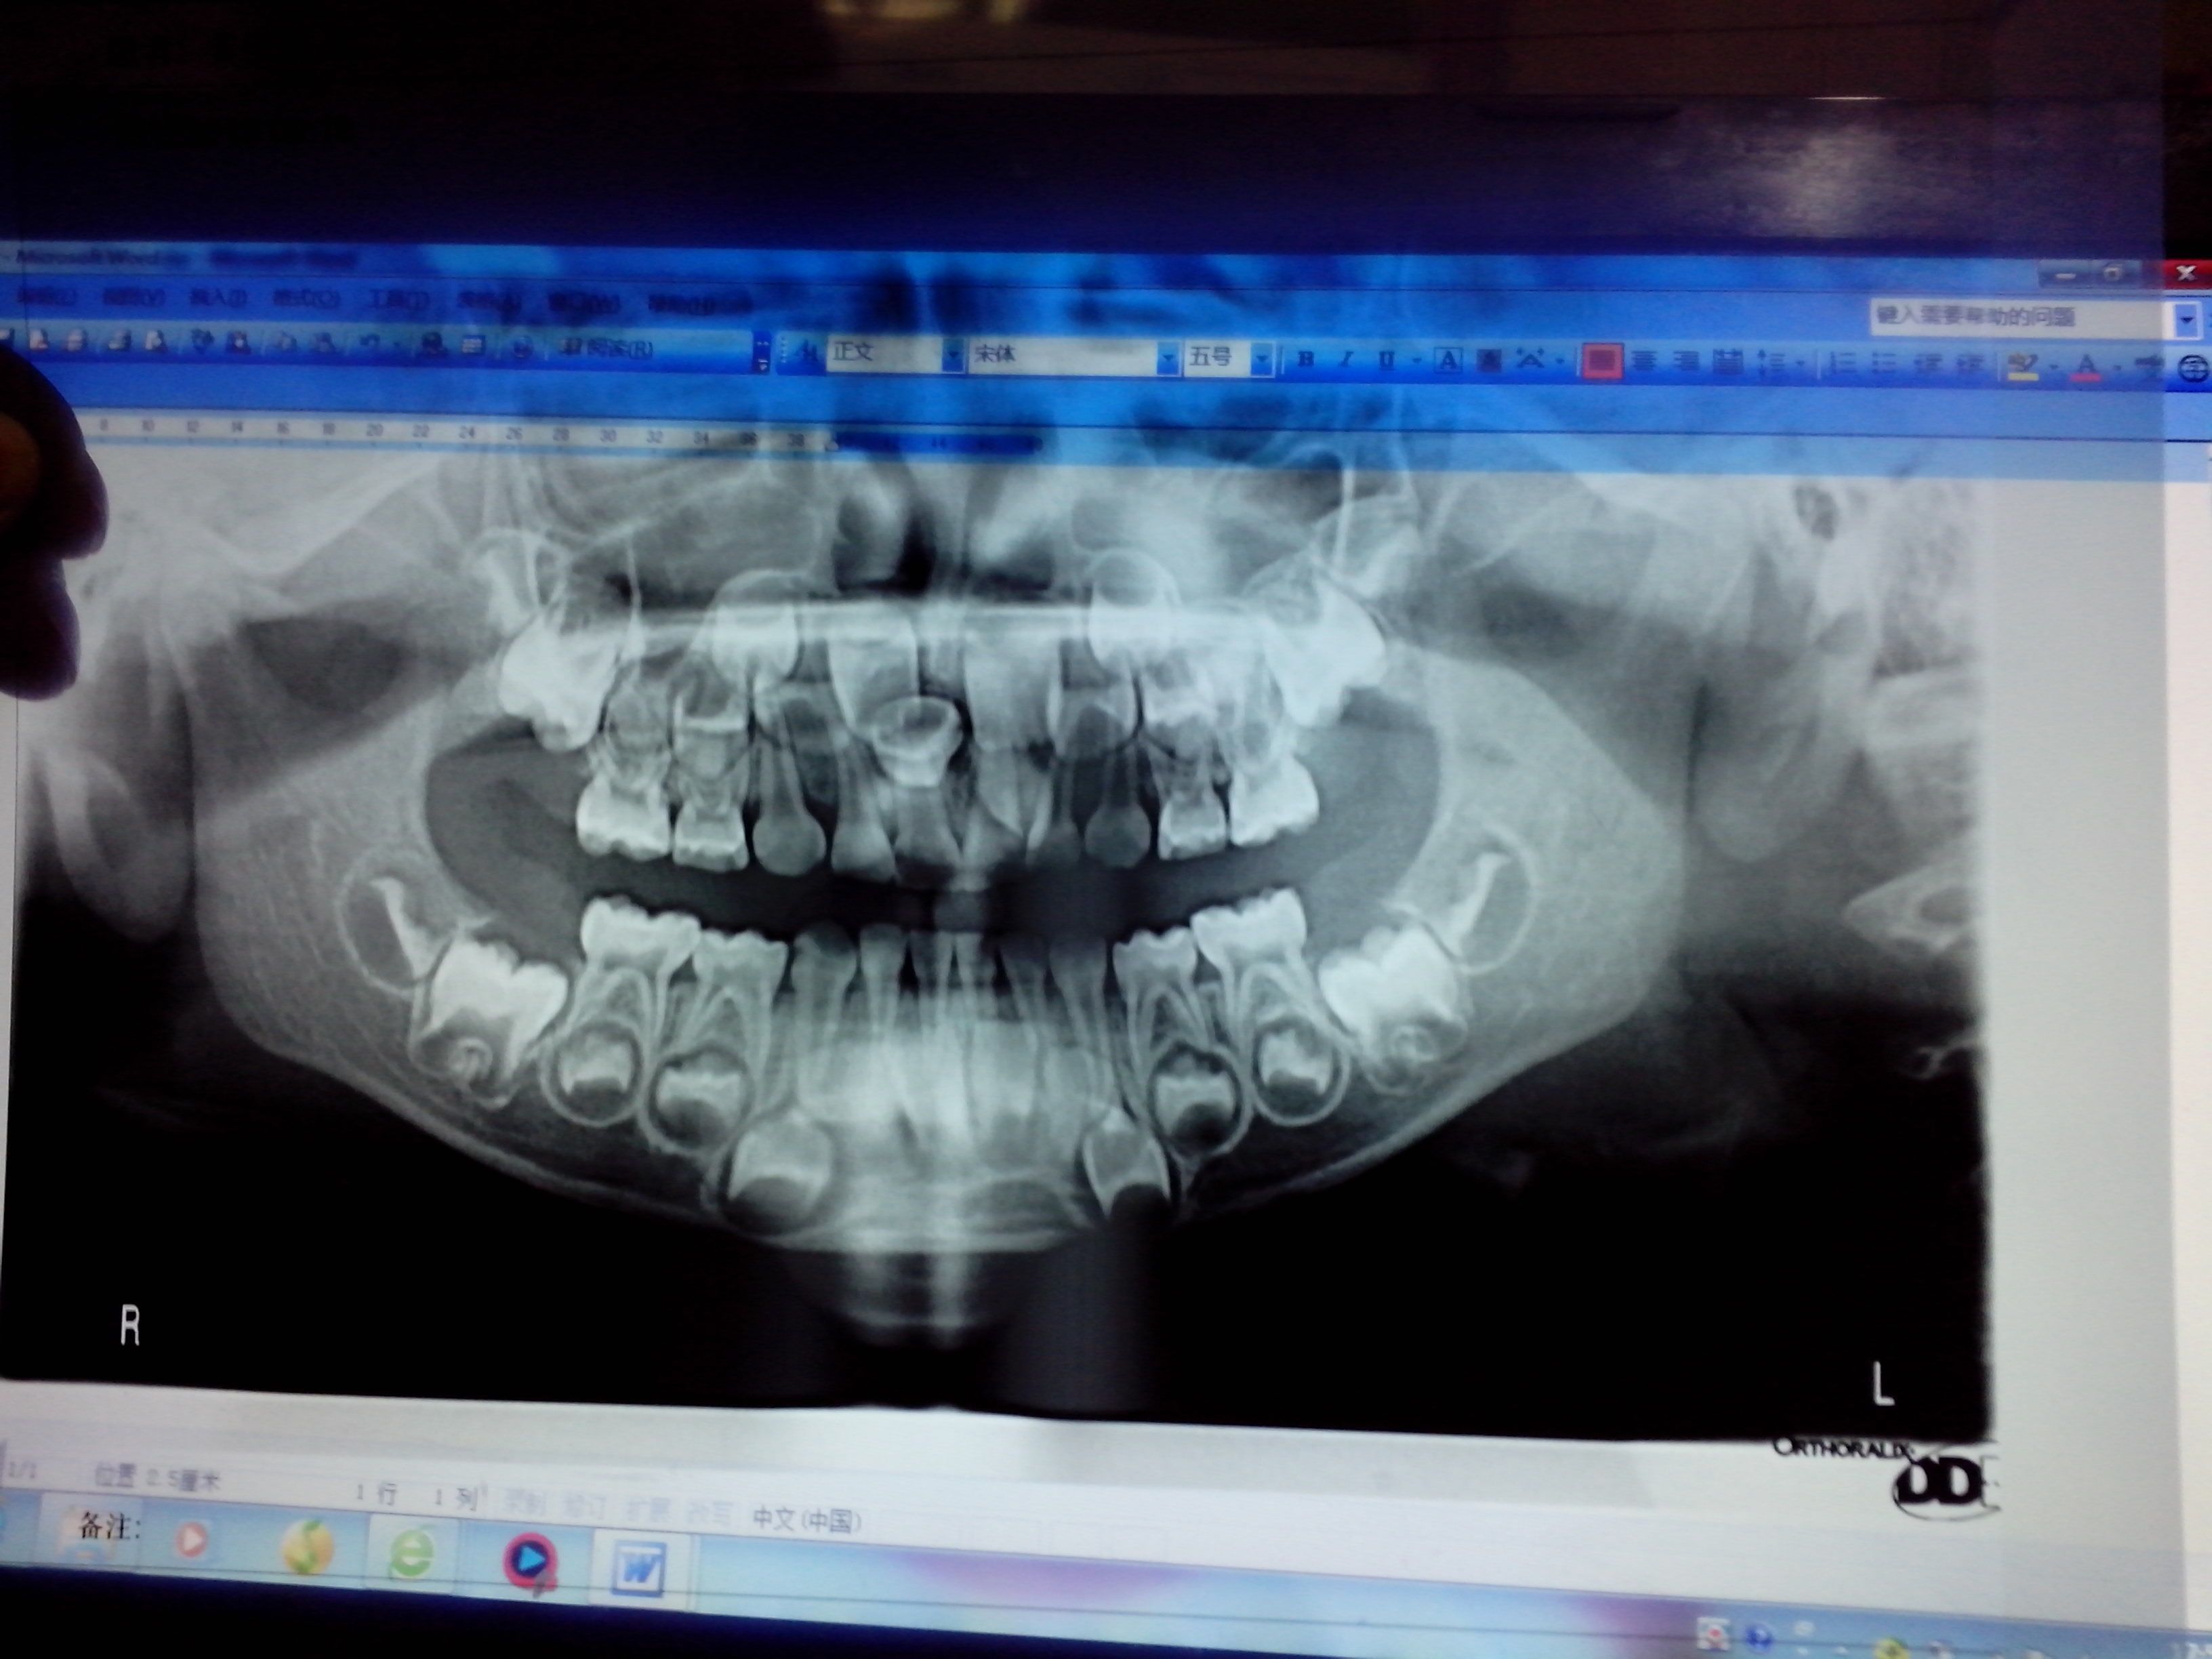

您好,我家宝宝现在四周岁,还没有换牙 但是发现上牙膛上长了一颗牙齿 拍了一张片子 大夫说挺麻烦的

病情分析: 看了你的片子,上颌前牙区有一颗多生牙,曲面断层片是看不出来颊舌向的,不知道在口腔内能不能直视到牙齿,如果无法直视的话,还要做CT检查确定位置。 指导意见: 多生牙的治疗就是要拔除多生牙,考虑孩子年龄小,一般不能配合拔牙术,所以可能要在全身麻醉下手术治疗了,建议到口腔颌面外科住院手术治疗。...祝你和孩子健康!